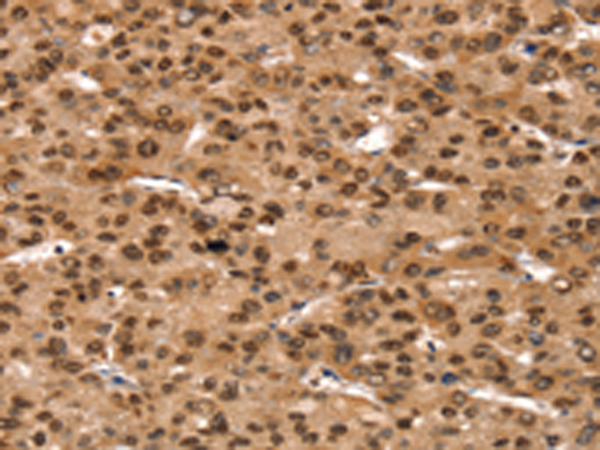

分类: 科研抗体货号: P05392别名: APT2; PSF2; ABC18; ABCB3; PSF-2; RING11; D6S217E应用: IHC反应种属: Human, Mouse, Rat